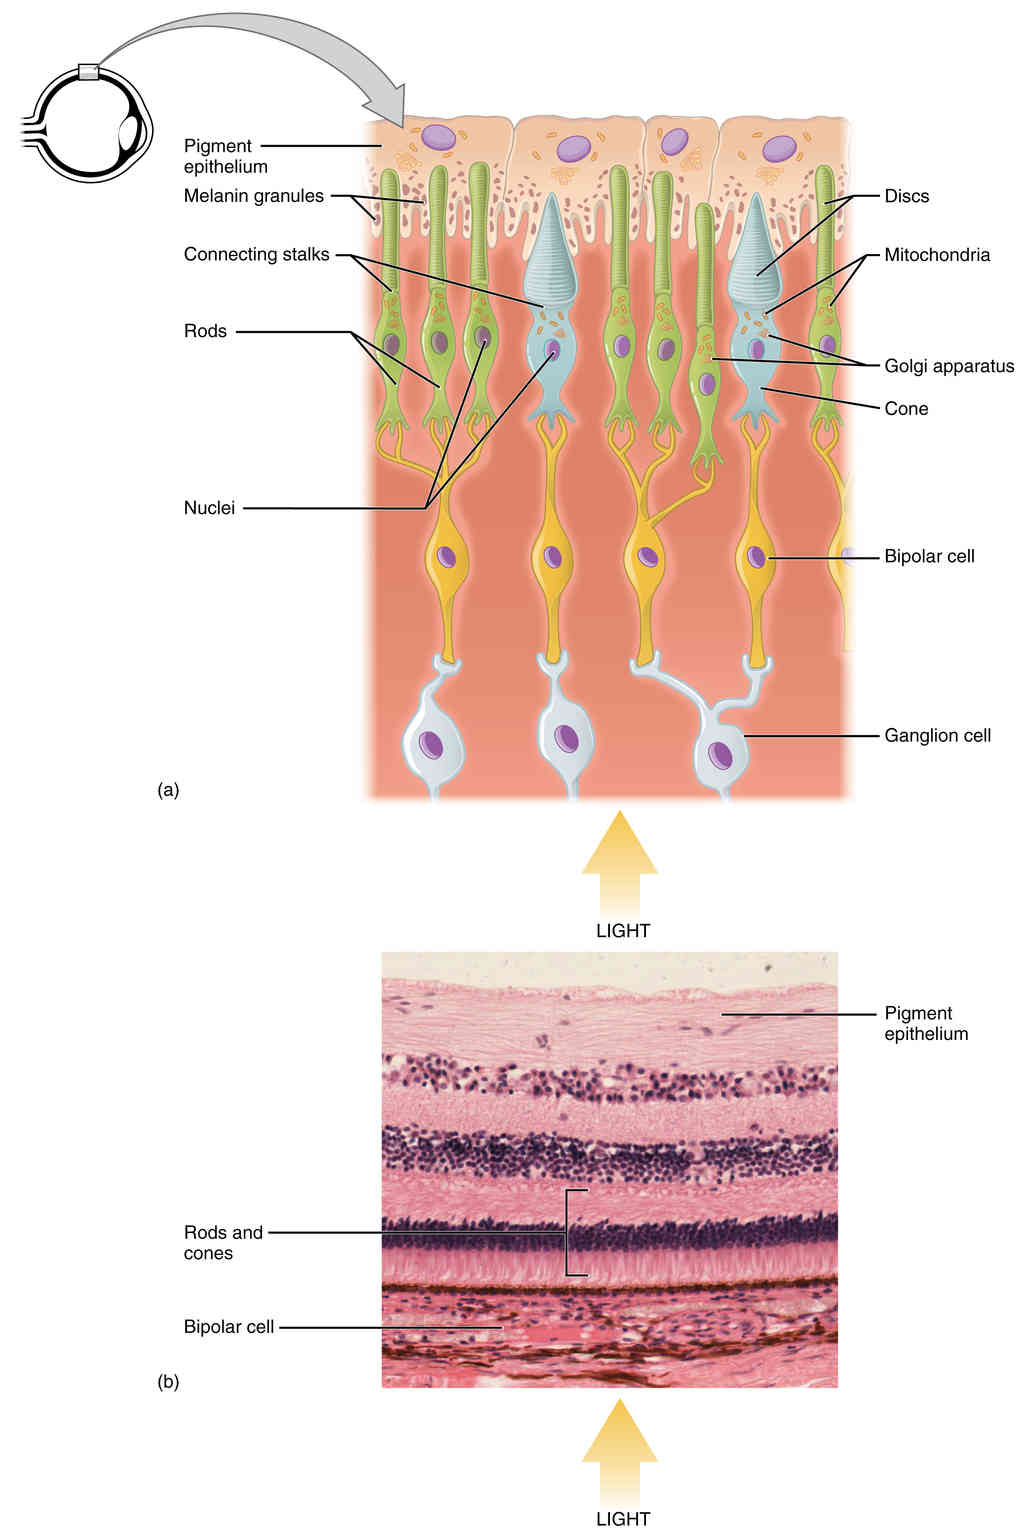

This page is under construction. For now, it is just a resource of the images found in the OpenStax Anatomy and Physiology Handbook. It wil slowly change into a revision tool. Each slide has a number. Use this to refer to the slide. When completed, it will have an unlabelled section, with labelled slides in parallel. On the unlabelled slides, write your answer and use the labelled slide to assess yourself. Keep track by also noting the number on each slide. Improvement at each attempt is important, more so than full marks on a first attempt.